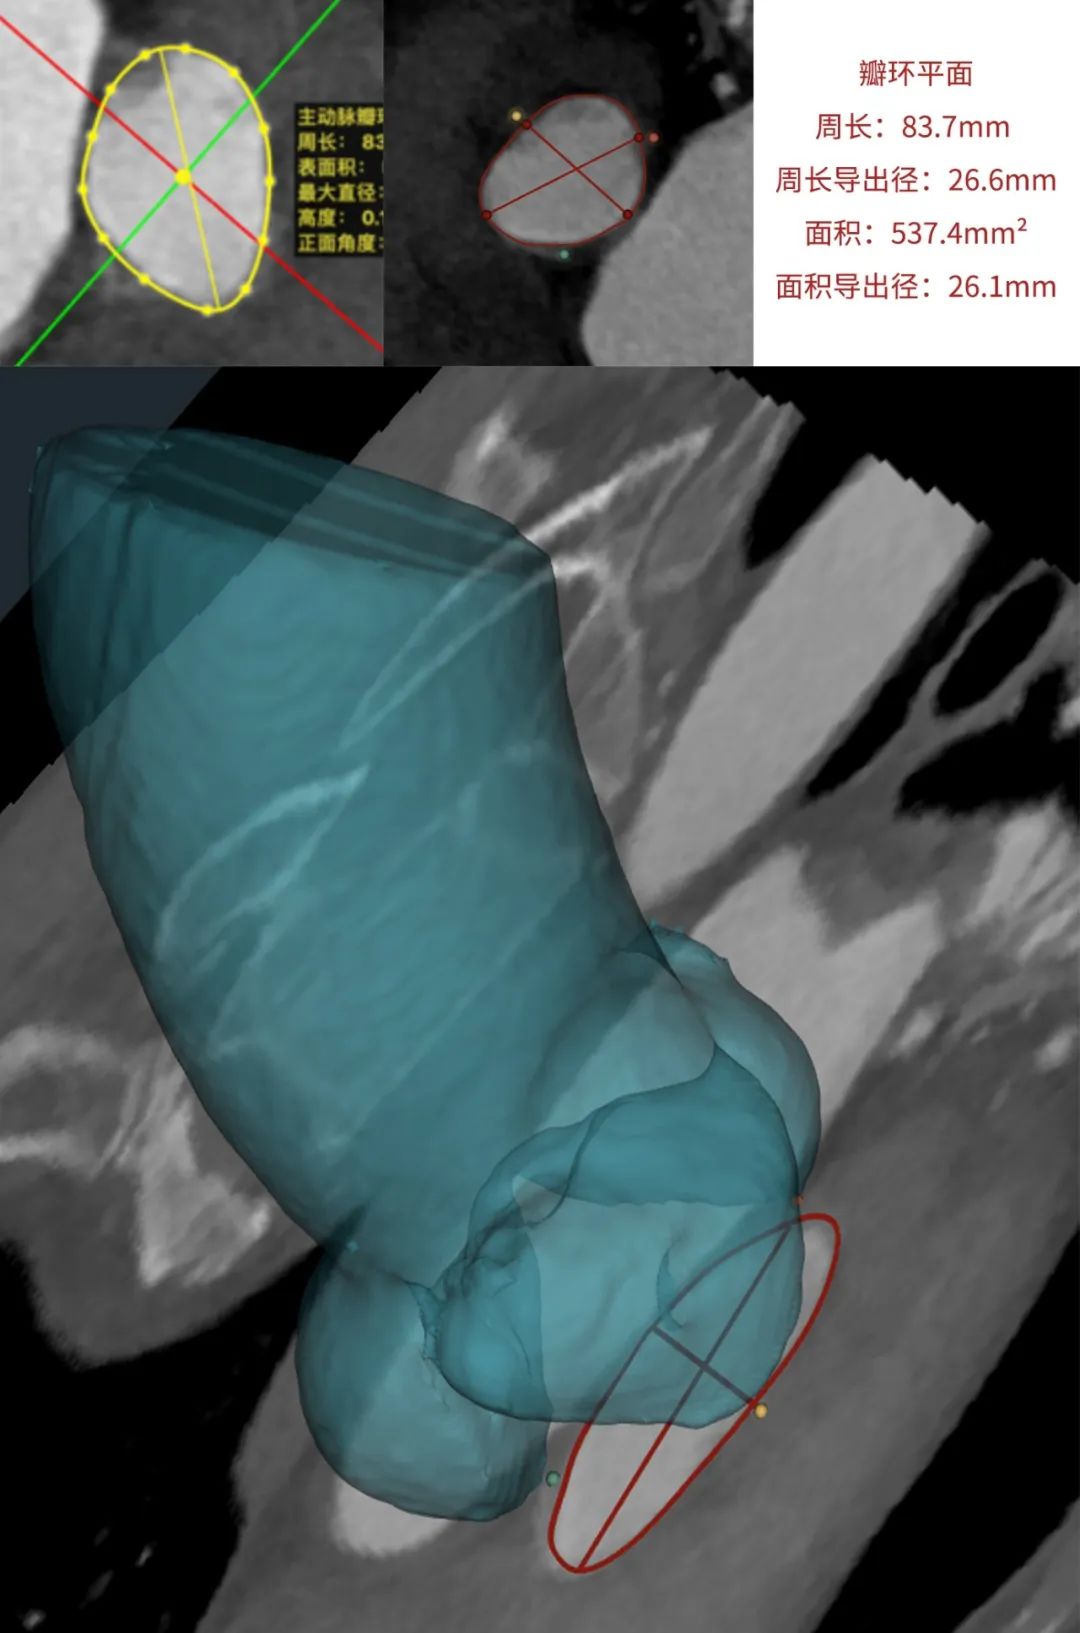

患者为68岁男性,因心悸胸闷入院。术前超声报告显示,患者为功能型二叶式主动脉瓣,右无融合钙化,主动脉瓣明显增厚钙化,瓣叶开放受限,主动脉瓣前向血流加速Vmax=4.2m/s,平均跨瓣压差36mmHg,有效开口面积0.7cm²,舒张期瓣口中度反流信号。

临床团队同时使用了基于医生手工描点的围术期影像评估软件和基于人工智能的瓣膜疾病围术期分析辅助决策软件进行术前影像学评估。

通过术前测量,对病例深入分析,结合人工智能术前分析辅助决策软件进行三维和二维图像融合,郭应强教授指出本例手术存在以下难点:

功能型二叶式主动脉瓣,瓣叶开口偏向一侧,瓣膜释放后存在不同轴可能。

选择植入Xcor-26瓣膜,充分利用支撑臂避免瓣膜移位发生。

标准位释放,双锚定实现生理性同轴以获得更优的血流动力学效果。

在LAO 9 CAU 24(左右窦重合体位)投照角度,瓣叶交界贴合释放。